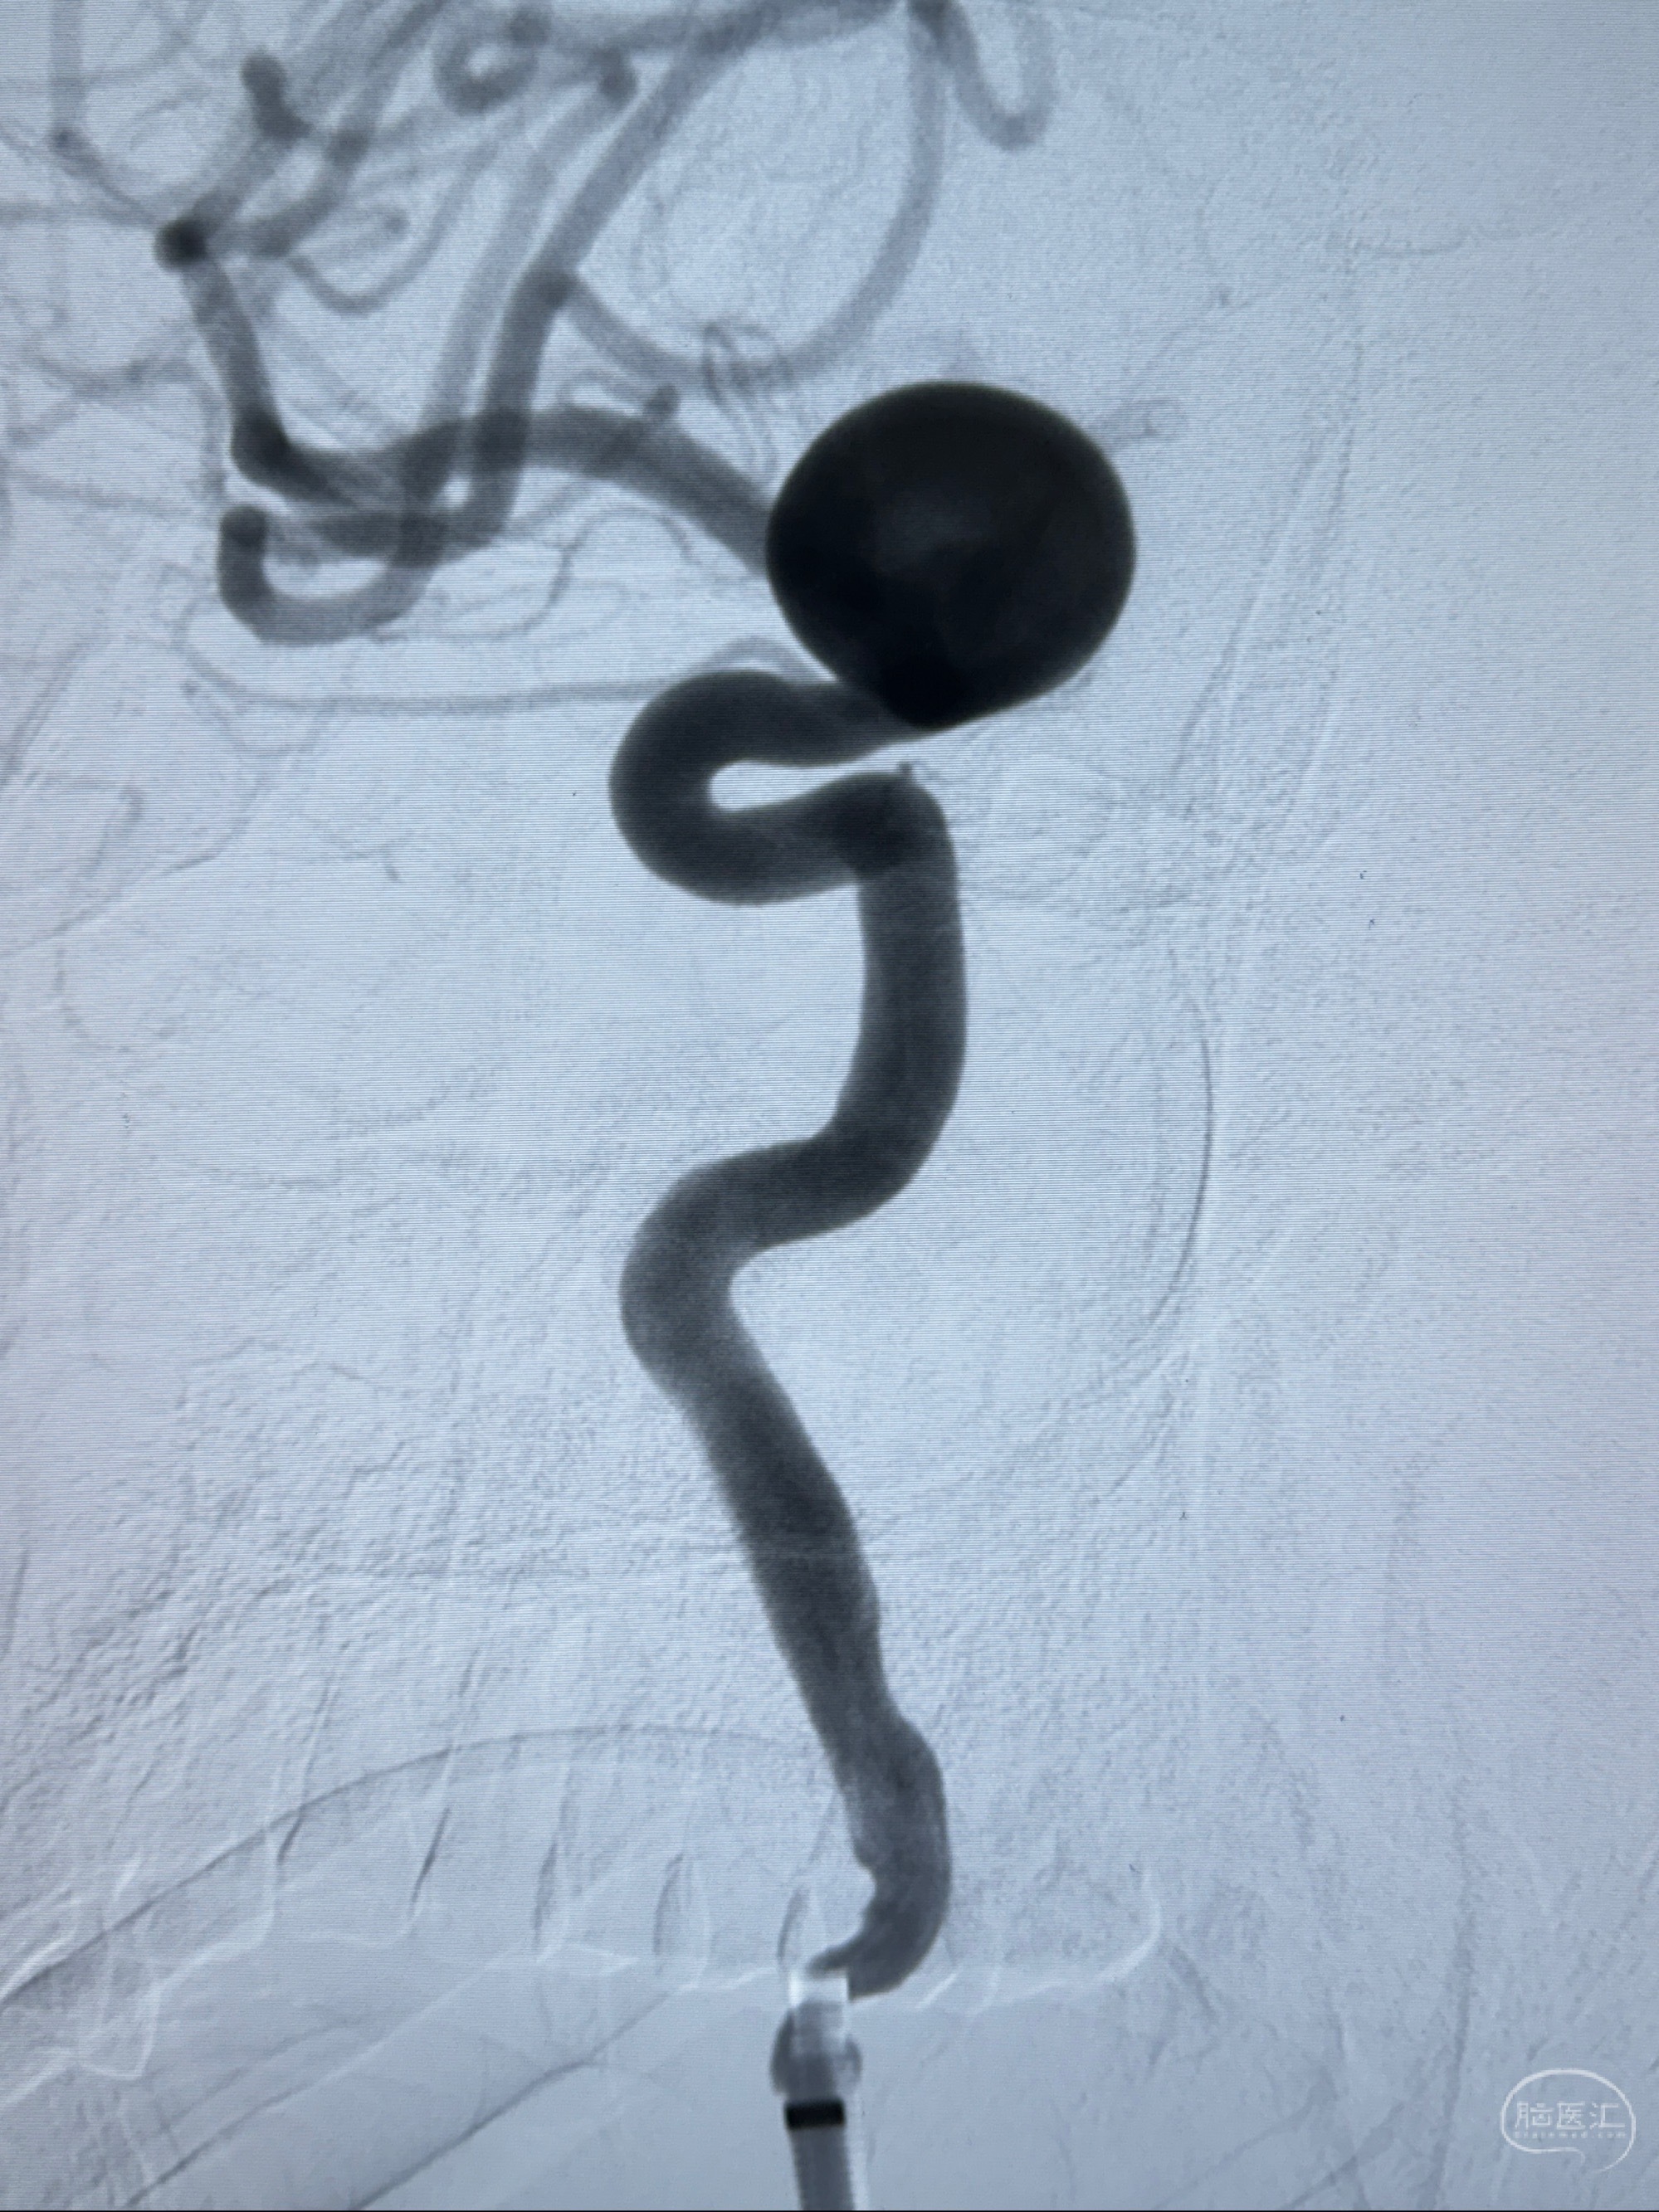

2023-12-08 复旦大学附属华山医院 全脑血管造影:右侧颈内动脉C6段动脉瘤,瘤颈6.68mm,动脉瘤大小13.28*12.34mm

2023-12-08外院DSA:右侧颈眼动脉瘤,约13*12mm大小,压颈试验显示左右向及后向前代偿可

测量动脉瘤的大小:16*13.8*7.6mm大小,较原先变大,考虑双抗后瘤内血栓溶解可能

观察动脉瘤腔内的血流动力学情况